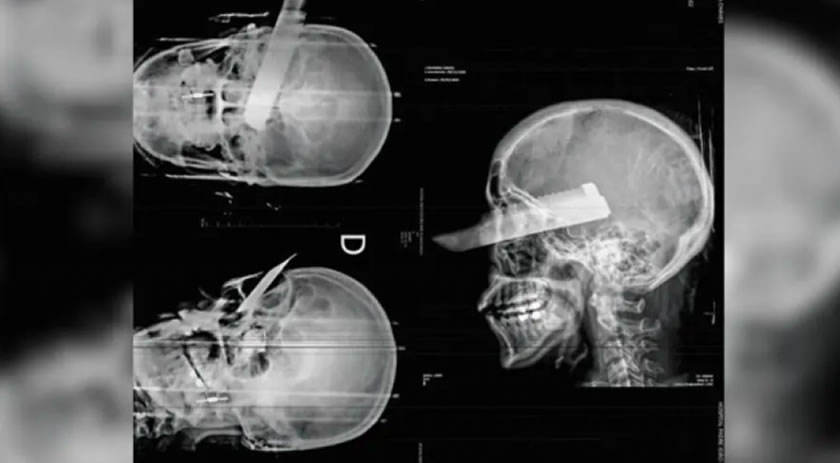

Uma mulher sofreu uma tentativa de feminicídio na manhã desta segunda-feira (2) em São Carlos, no Oeste de Santa Catarina, ao ser atacada pelo companheiro dentro da residência do casal. O agressor desferiu um golpe de faca no rosto da vítima, atingindo o olho direito, mas o crime não se consumou, segundo a polícia, graças ao pronto atendimento médico.

Conforme apurado pela Polícia Civil, o suspeito agiu com a intenção de a matar. A vítima conseguiu escapar parcialmente da agressão, mas foi atingida enquanto tentava fugir. Ela recebeu atendimento de emergência e passa por acompanhamento médico.